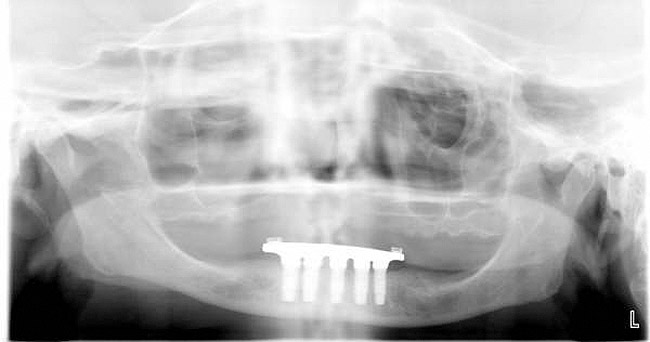

Figure 11a  Insufficient crown height space for bar overdenture because of the vertical dimension of the mandible.

Figure 11a

Figure 11b  Osteoplasty performed at the time of implant placement to gain sufficient crown height space.

Figure 11b